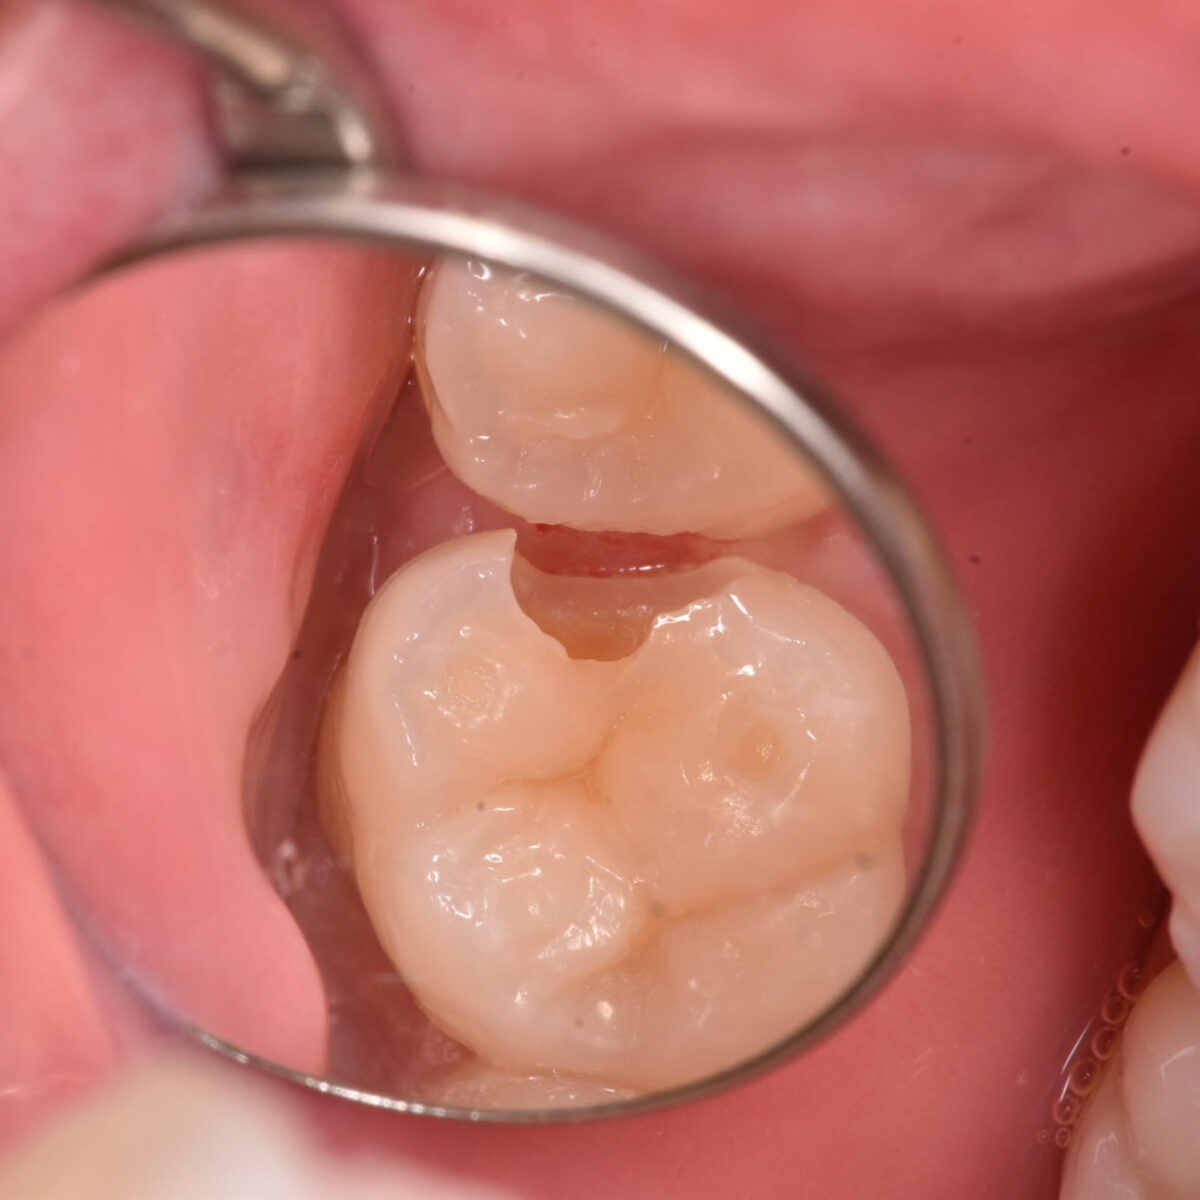

痛みがなければ虫歯じゃないの?2

症状がなければ問題はないのか? 【東京メトロ東西線妙典駅 徒歩5分の歯医者】市川、妙典の歯科医院、めぐりデンタルクリニックの梶原です。 前回に続いて記事を書きます。前回記事について…